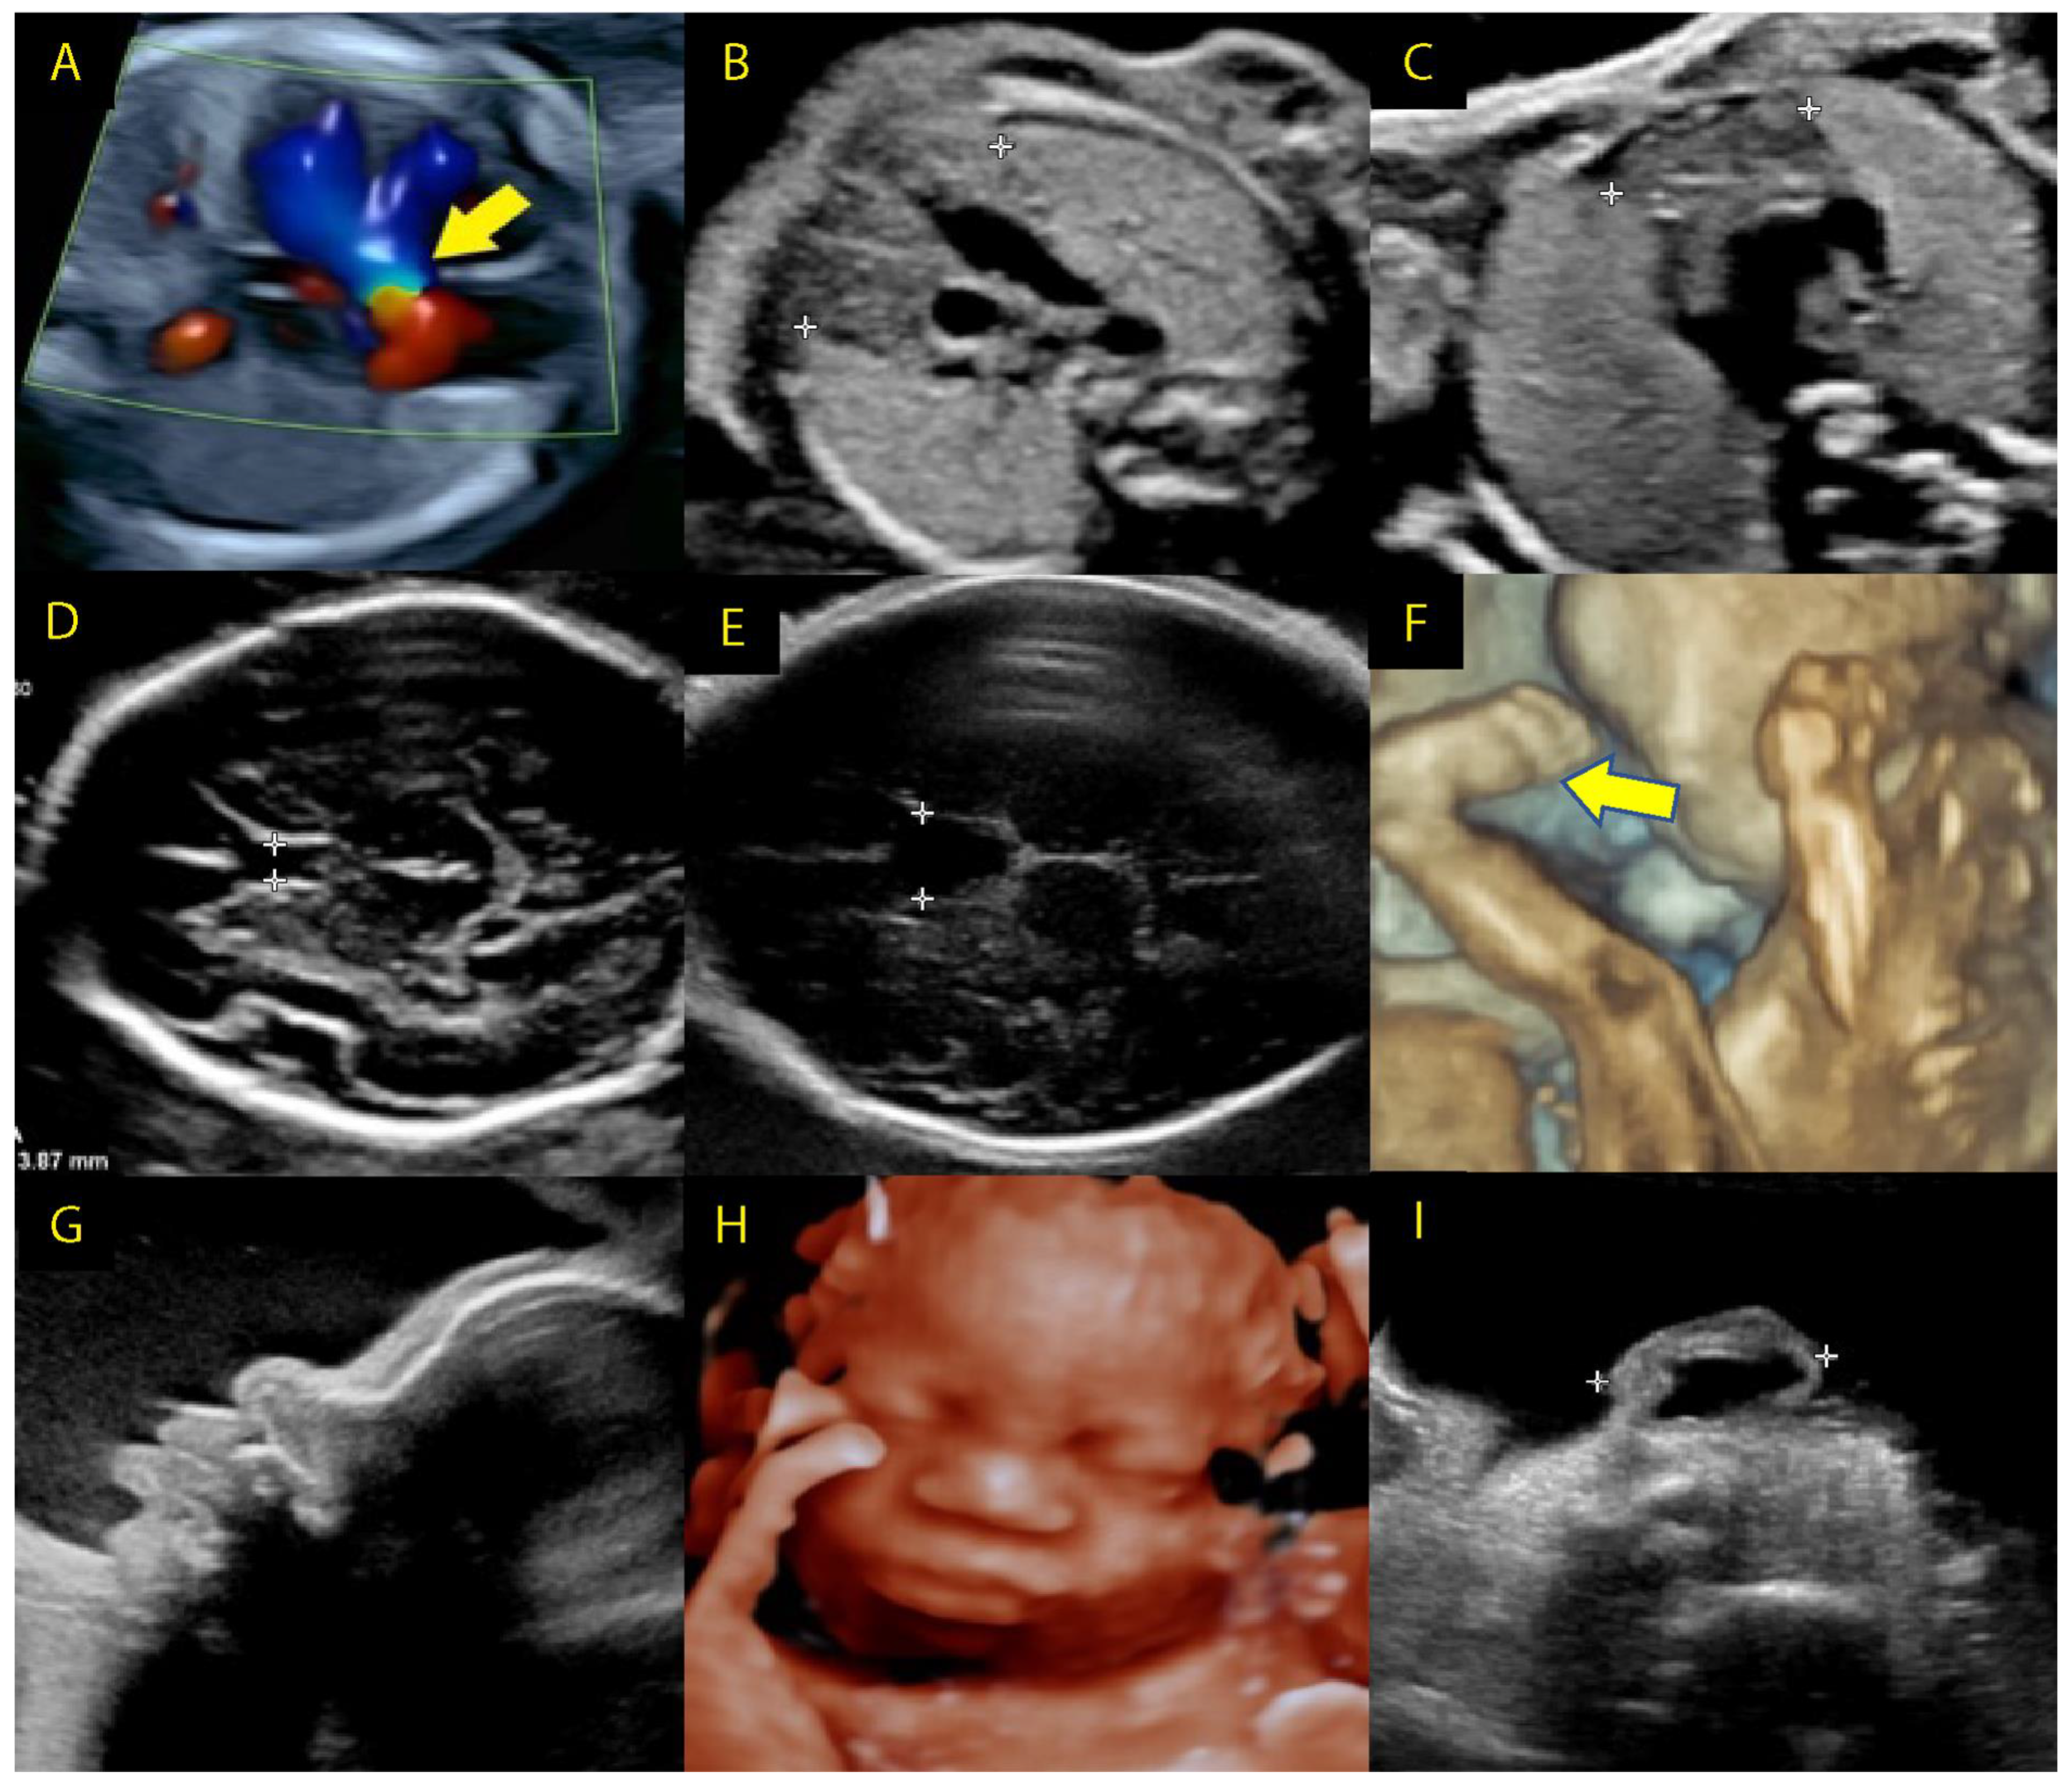

3.1.3. Prenatal Screening—Ultrasound Imaging in 22q11.2 Microdeletions

3.1.4. First-Trimester Ultrasound

3.1.5. Second-Trimester Ultrasound

3.1.6. Third-Trimester Ultrasound

- Li, L.; Bahtiyar, M.O.; Buhimschi, C.S.; Zou, L.; Zhou, Q.-C.; Copel, J.A. Assessment of the Fetal Thymus by Two- and Three-Dimensional Ultrasound during Normal Human Gestation and in Fetuses with Congenital Heart Defects. Ultrasound Obstet. Gynecol. 2011, 37, 404–409. [Google Scholar] [CrossRef]

- Chaoui, R.; Kalache, K.D.; Heling, K.S.; Tennstedt, C.; Bommer, C.; Körner, H. Absent or Hypoplastic Thymus on Ultrasound: A Marker for Deletion 22q11.2 in Fetal Cardiac Defects. Ultrasound Obstet. Gynecol. 2002, 20, 546–552. [Google Scholar] [CrossRef]

- Chaoui, R.; Heling, K.-S.; Sarut Lopez, A.; Thiel, G.; Karl, K. The Thymic–Thoracic Ratio in Fetal Heart Defects: A Simple Way to Identify Fetuses at High Risk for Microdeletion 22q11. Ultrasound Obstet. Gynecol. 2011, 37, 397–403. [Google Scholar] [CrossRef]

- Chaoui, R.; Heling, K.-S.; Zhao, Y.; Sinkovskaya, E.; Abuhamad, A.; Karl, K. Dilated Cavum Septi Pellucidi in Fetuses with Microdeletion 22q11. Prenat. Diagn. 2016, 36, 911–915. [Google Scholar] [CrossRef] [PubMed]

- Pylypjuk, C.L.; Memon, S.F.; Chodirker, B.N. Utility of Measuring Fetal Cavum Septum Pellucidum (CSP) Width During Routine Obstetrical Ultrasound for Improving Diagnosis of 22q11.2 Deletion Syndrome: A Case-Control Study. Appl. Clin. Genet. 2022, 15, 87–95. [Google Scholar] [CrossRef] [PubMed]